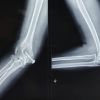

The standard anterior-posterior and lateral radiographs of the right elbow joint showed circumferential calcification with a radiolucent center (Fig. 1a and b). Complete blood workup and erythrocyte sedimentation rate values were within normal. Considering the age and demand of the patient, surgical excision was executed. The patient was taken up for an operative procedure under general anesthesia with the patient in a supine position and a limb abducted at the shoulder. The elbow range of motion was checked and found to have fixed flexion deformity at 75° (Fig. 2). Through the anterior approach, a 9 cm curvilinear skin incision was made. Subcutaneous tissue and deep fascia were incised in the skin incision line, muscles were retracted. Care was taken to identify the neurovascular bundle and then retracted. The irregular calcified mass was adequately exposed and was excised (Fig. 3a and b). Similarly, through the posterior approach, a skin incision was made, subcutaneous tissue, and fascia dissected, muscles retracted, and calcified mass was visualized over the olecranon process and fibrous tissue in olecranon fossa which was excised (Fig. 3c).

The elbow was mobilized intra-operatively. The post-operative period was uneventful. Elbow joint mobilization was started from day 2. There was no motor/sensory deficit. The excised sample which was sent for histopathological examination revealed lamellar bone centrally. Radio graphical examination postoperatively revealed no abnormal mass in the elbow (Fig. 4a and b). The patient was discharged in post-operative on day 10 after suture removal and was asked to continue elbow mobilization exercises. The patient underwent follow-ups at 2 weeks, 4 weeks, 6 weeks, 10 weeks, 14 weeks, 3 months, and every 6 months thereafter. He was able to return to his routine lifestyle in 10 weeks. Elbow flexion was checked and the range of movements was found to have increased to 45–90° at the 6-month follow-up (Fig. 5a and b). The patient regained function and was able to eat food and comb his hair with his right hand. The patient recovered with the best attainable functional status at 2 years. Radiographic or clinical recurrence was not detected at any follow-up.